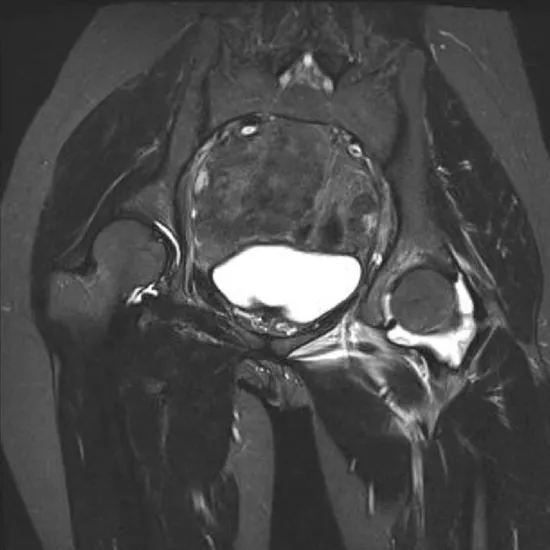

Contrast-enhanced MRI of the left hip joint visualizes the hip joint, its bones, and surrounding soft tissues such as tendons, ligaments, muscles, and blood vessels. Therefore, the contrast enhances the MRI scan's sensitivity and diagnostic accuracy by improving the internal organs' visibility.

This test is used to diagnose any fractures of the bones that compose the hip joint and any suspected hip dislocation or arthritis of this joint.